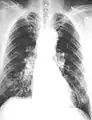

Extensive fibrosis of pleura and lung parenchyma.

61 yr old working industrially with asbestos for decades.